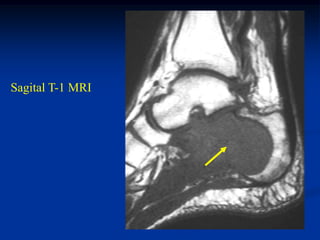

Case #1130            Metastatic Renal Cell

45 year male with metastatic renal cell CA to os calcis

Sagital T-1 MRI

tumor